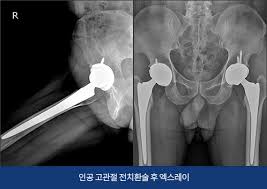

- 인공관절 치환술: 가장 일반적인 고관절 수술입니다. 퇴행성 관절염이나 심한 외상으로 인해 고관절이 손상된 경우, 인공 관절로 대체합니다. 이 수술은 대개 1-2시간 가량 소요되며, 회복이 길어질 수 있습니다.

- 진단적 검사: 의사가 필요할 경우 정기적으로 X-ray나 MRI를 통해 관절의 상태를 체크할 수 있습니다.